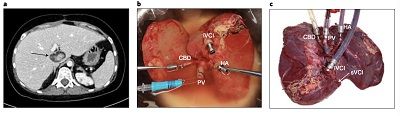

英国《自然·生物技术》杂志31日公开的一篇医学论文称,一名接受利用机械灌注技术在体外保存三天的人类肝脏的移植患者,在术后一年依然身体健康。这项技术或能扩大可移植肝脏的数量,同时有望为患者安排择期手术,从而拯救更多生命。

瑞士苏黎世大学医院团队一直致力于延长肝脏的体外保存时间。在最新的报告中,研究人员皮埃尔-阿兰·凯文及其同事利用一台机器,将一个人类肝脏在体外保存 了三天,这个机器能操作名为“体外常温灌注”的技术,该技术能为体外的肝脏提供处于正常体温的“代血液”,核心则是模仿生理学上关键的身体功能。

这个肝脏随后被移植到了一名晚期肝硬化和严重门静脉高压症等多种严重肝病患者的体内。移植后的肝脏能正常工作,来自体内血管的血流恢复后,只出现了很小的损伤,且移植后的第一个6周内只需使用基本免疫抑制方案。

这名患者的生活质量很快得到了恢复,而且没有任何肝损伤的迹象,如排异或胆管损伤,患者术后一年依然健康。